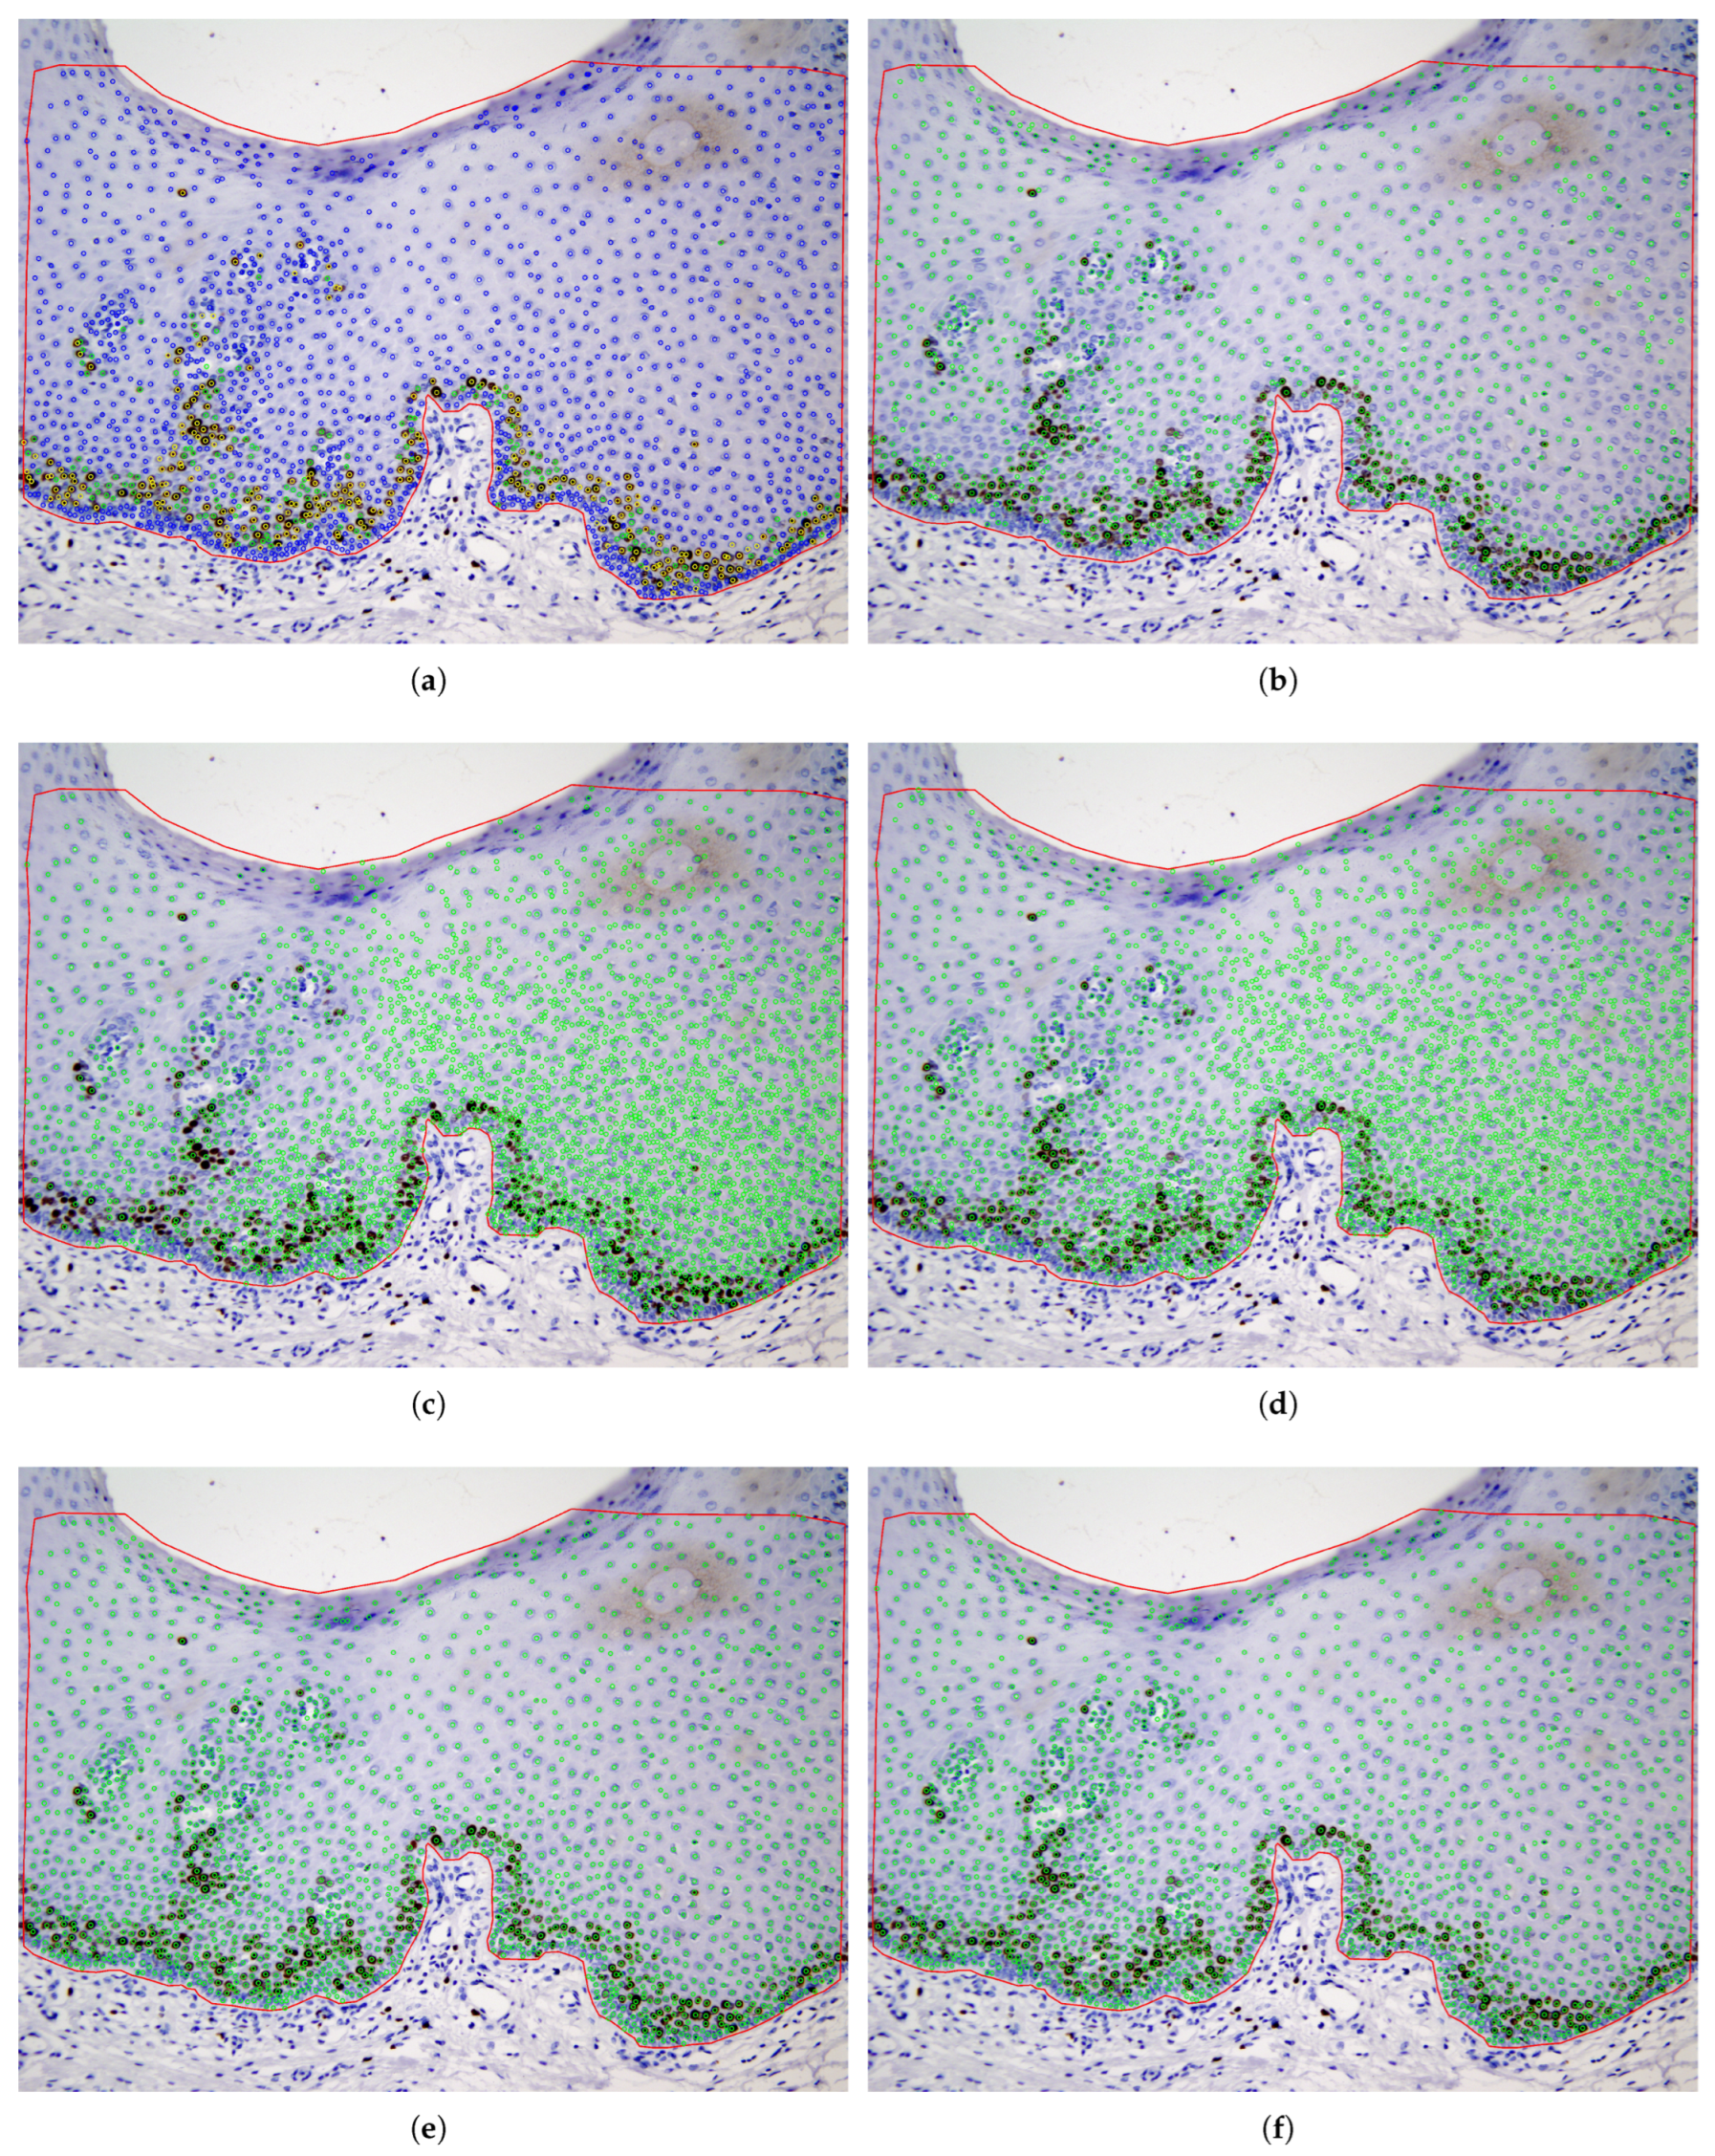

4.4. Cell Detection Using Deep Learning